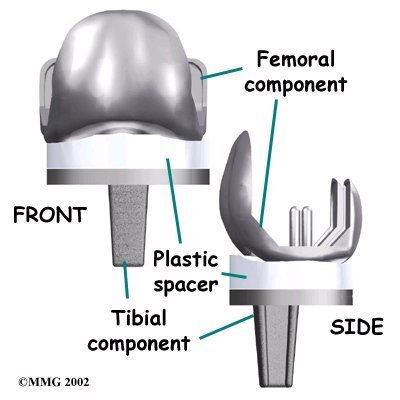

Each prosthesis is made up of three main parts.

The tibial component (bottom portion) replaces the top surface of the lower bone, the tibia. The femoral component (top portion) replaces the bottom surface of the upper bone (the femur) and the groove where the patella fits. The patellar component (kneecap portion) replaces the surface of the patella where it glides in the groove on the femur.

The femoral component is made of metal. The tibial component is usually made of two parts: a metal tray that is attached directly to the bone, and a plastic spacer that provides the slick surface. The plastic used is so tough and slick that you could ice skate on a sheet of it without damaging the material much. The patellar component is usually made of plastic as well. In some types of knee implants, the patellar component is made of a combination of metal and plastic.